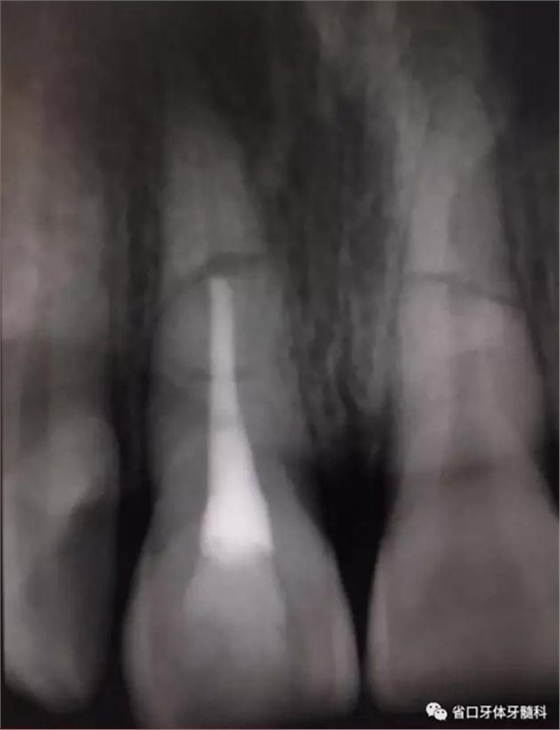

圖6 斷端MTA封閉術(shù)后

圖7 熱牙膠根充片